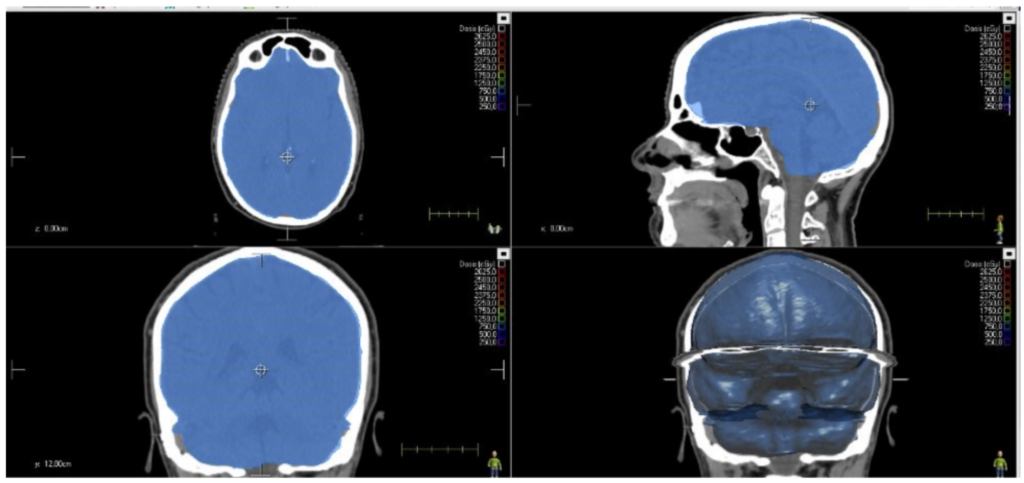

Las funciones del técnico de Radioterapia y Dosimetría en las distintas etapas clínicas del tratamiento radioterápico aparecen en el Real Decreto 772/2014. También se presentan en el Real Decreto 391/2025 de criterios de calidad y seguridad en las unidades asistenciales de radioterapia. Entre ellas se incluye la colaboración en la delimitación de órganos de riesgo (OAR). La herramienta de aprendizaje y entrenamiento OAR-Train capacita a los estudiantes del ciclo superior en esta crucial tarea para la seguridad del paciente.

La comunidad OAR-Train se expande con la reciente incorporación de la herramienta de aprendizaje y entrenamiento OAR-Train en C.I.F.P. Ánxel Casal-Monte Alto (A Coruña). El recurso digital se usará en el Ciclo Superior de Radioterapia y Dosimetría para capacitar a los estudiantes en la correcta delimitación de órganos de riesgo (OAR).

FP Santa Gema (Madrid) ahora forma parte de la comunidad OAR-Train, tras metrodora FP (Centro de Excelencia metrodora FP-Cámara en Madrid), el C.I.F.P. Camino de la Miranda (Palencia) y BiG Formación (Ourense). OAR-Train les permite entrenar a los alumnos de Radioterapia y Dosimetría en la correcta delimitación de órganos de riesgo (OAR) en un entorno seguro y comparar sus resultados con el gold standard de los expertos.